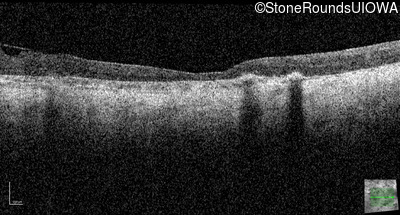

Optical Coherence Tomography - Right - No Light Perception

Exemplar / OCT Stack